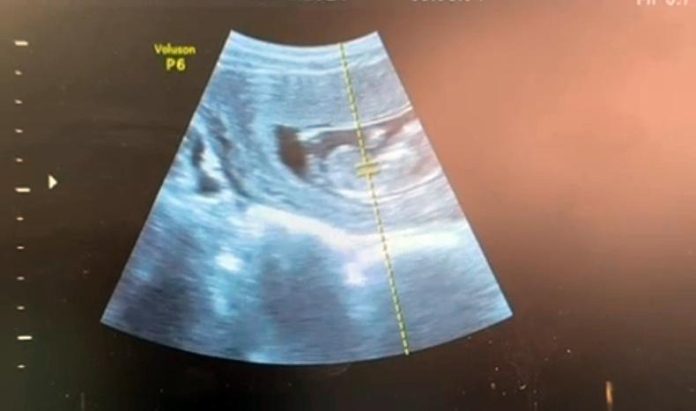

Operația a decurs favorabil. La ecografia efectuată postoperator, medicii au confirmat prezența bătăilor cordului fetal, un rezultat considerat esențial pentru evoluția sarcinii.

Intervenția a fost realizată de o echipă medicală formată din medicul operator dr. Florin Mitocaru, medicul ajutor dr. Rodica Lazăr și medicul anestezist dr. Iurie Bostan. Diagnosticul ecografic a fost stabilit de dr. Virginia Beceru, cu sprijinul echipei de asistenți medicali.